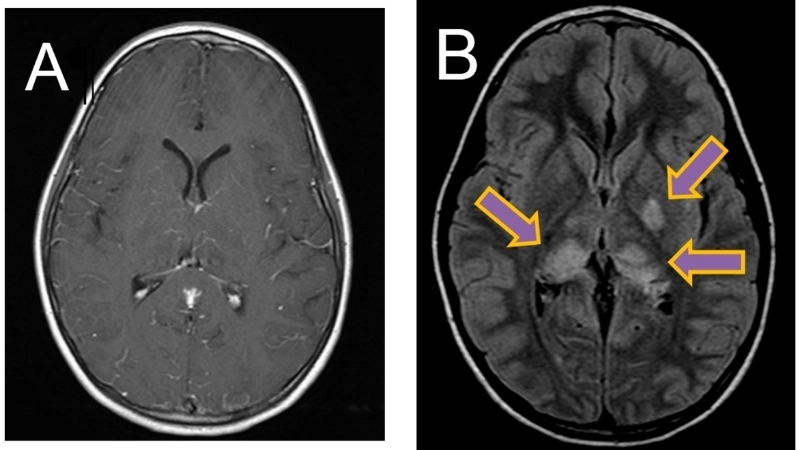

Image description of Murray Valley Encephalitis

Murray Valley Encephalitis is a rare but serious viral infection transmitted by mosquitoes, primarily affecting the brain and nervous system, with potential life-threatening complications.